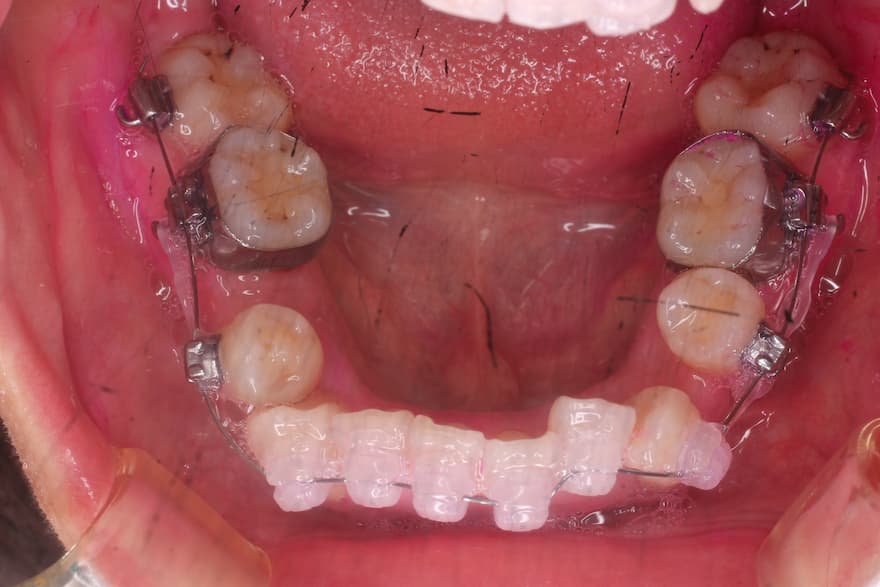

ブラケット装着